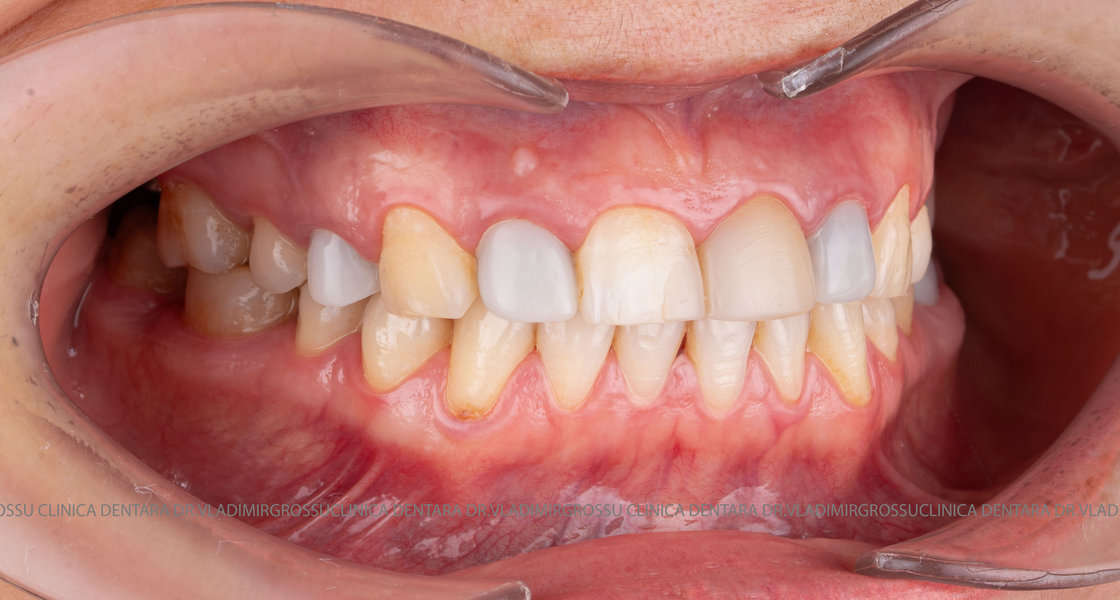

Caz 2

Restaurări cu coroane din zirconiu vs fațete ceramice

Transformările estetice și impactul reabilitării asupra vieții pacienților

Reabilitarea dentară produce o schimbare vizibilă și profundă în aspectul pacientului, cu efecte pozitive evidente asupra stimei de sine și a calității vieții. Mulți pacienți relatează bucuria redobândirii funcției masticatorii și dispariția complexelor legate de aspectul dentar.